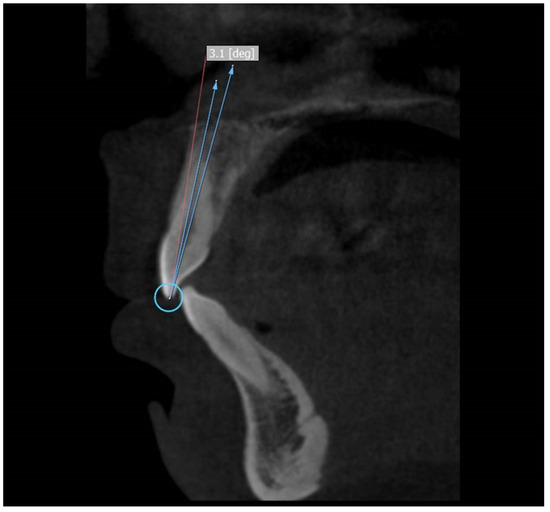

2.2. Studied Parameters

2.3. Measurement of Crown to Root Angle (x)